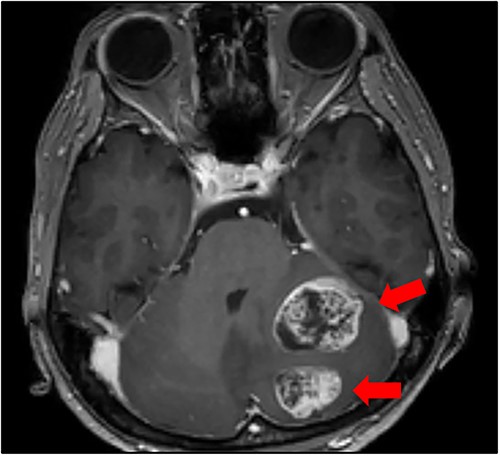

Cranial magnetic resonance imaging (MRI) showed two nearby ring-shaped enhanced tumours with maximum diameters of 3.3 and 2.4 cm in the left cerebellum (Fig. 3). Contrast-enhanced computed tomography (CT) revealed swelling of the left adrenal gland with a maximum diameter of 6 cm (Fig. 4). Positron emission tomography showed other high fluorine-18-deoxyglucose accumulations without the above lesions. The tumour markers, including CEA, CA19-9, and CA125, were within normal ranges. The cerebellar tumours were resected and diagnosed because the patient had neurological symptoms. Histopathological findings of the resected specimens indicated signet-ring cell carcinoma (Fig. 5), which was diagnosed as metastatic gastric cancer. Resection of intracranial tumours rapidly improved her neurological disturbances.

Cranial MRI findings (T1-weighted image). Two ring-enhanced masses with maximum diameters of 3.3 and 2.4 cm were observed in the left cerebellum.